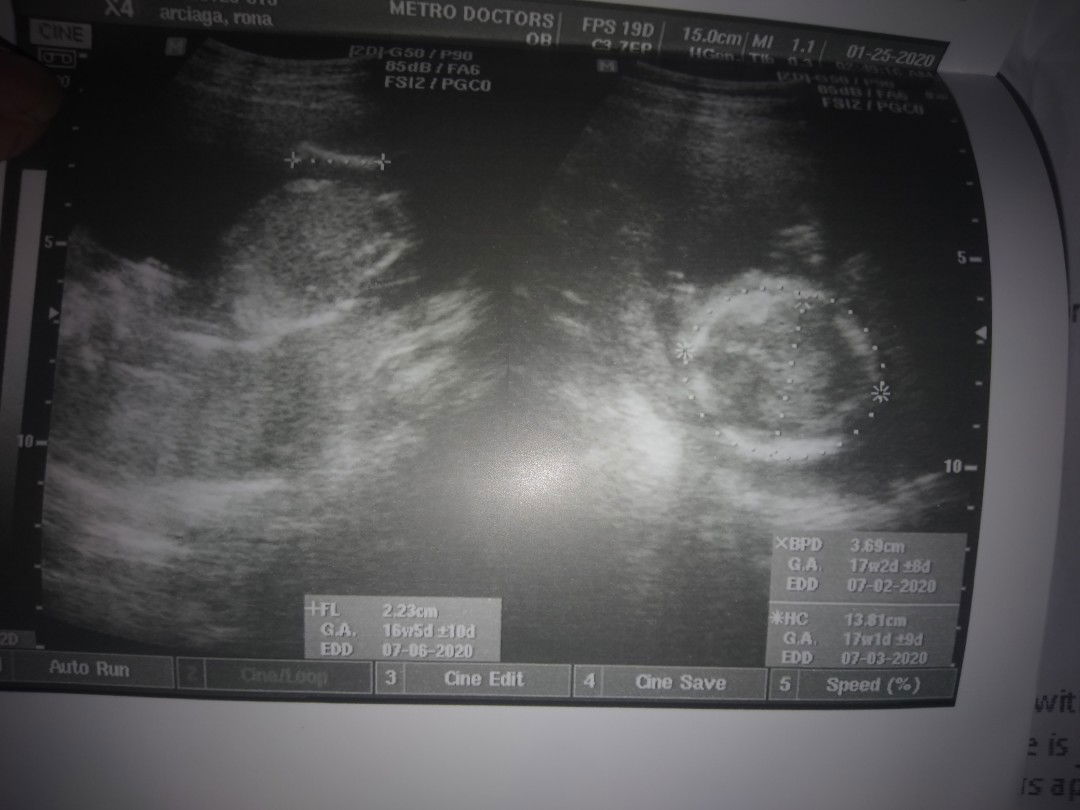

Yung head po ni baby ay yung nasa right side. Un lagi sinusukat ng ob ko na head part ni baby para malaman kung ilang weeks ung size ni baby

yung bilog na may dot dot yan yung ulo at sinusukat ng ultrasoundyl yung size ng ulo ng baby mo